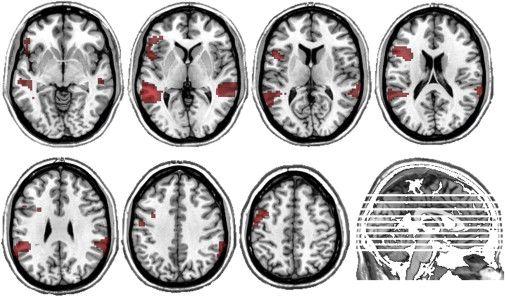

随着医学和神经科学的发展,人类对智力的研究已经进入更高的维度。fMRI这样的影像学手段,被用于评估大脑的区域功能表现,分子水平的研究使我们更深入的理解智力的原理。

hbf小组,求分享黑蝙蝠hbf合集!(被无数人接受的智商测试)

fMRI定位的语言能力的功能和解剖位置关联性